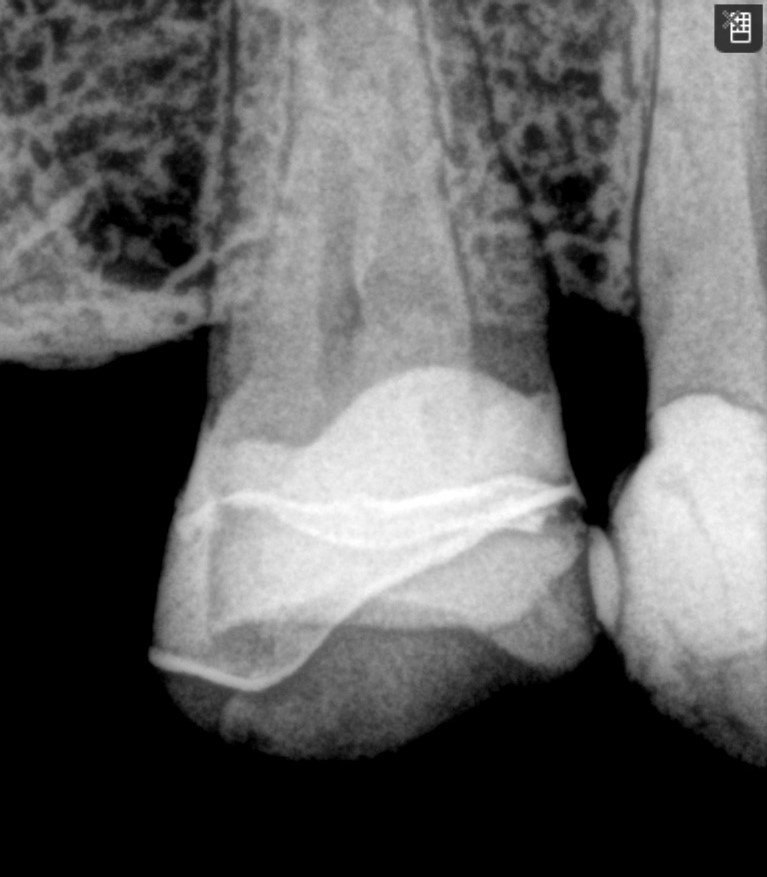

It has been years since I prepped below the height of contour and invaded the biorim, but here we are back at Day 0. By the time I removed caries and old composite and reduced the thin lingual cusps, all that was left was connecting the margins at the line angle. I’ll be honest, for a split second, I thought about filling in all the defects with direct composite, but I did not because I was running late.